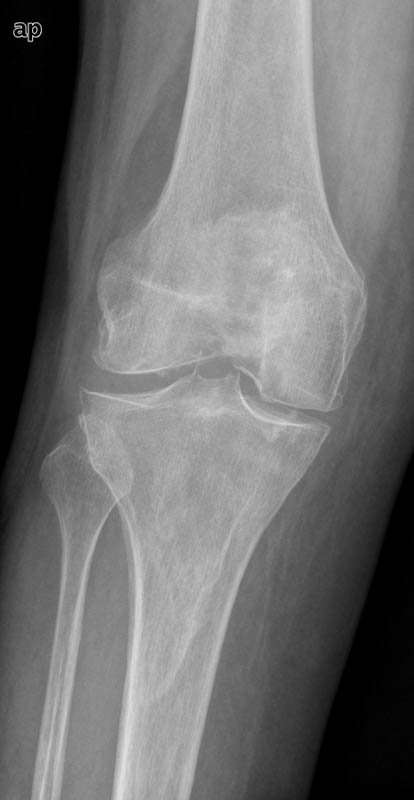

APR Gonartrosis